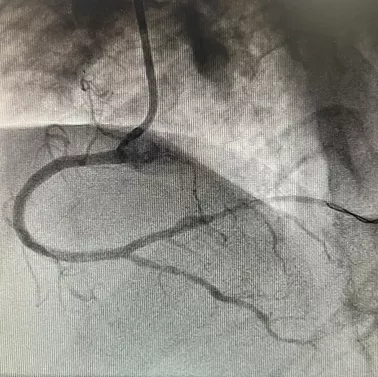

成功透過血管內膜下重新進入遠端血管真腔,經過多體位投照、逆向造影均證實為真腔,順利開通閉塞病變。

正向造影可見右冠全程瀰漫狹窄病變

序貫植入4枚第二代藥物洗脫支架覆蓋病變。

無術中併發症,手術完美收官。